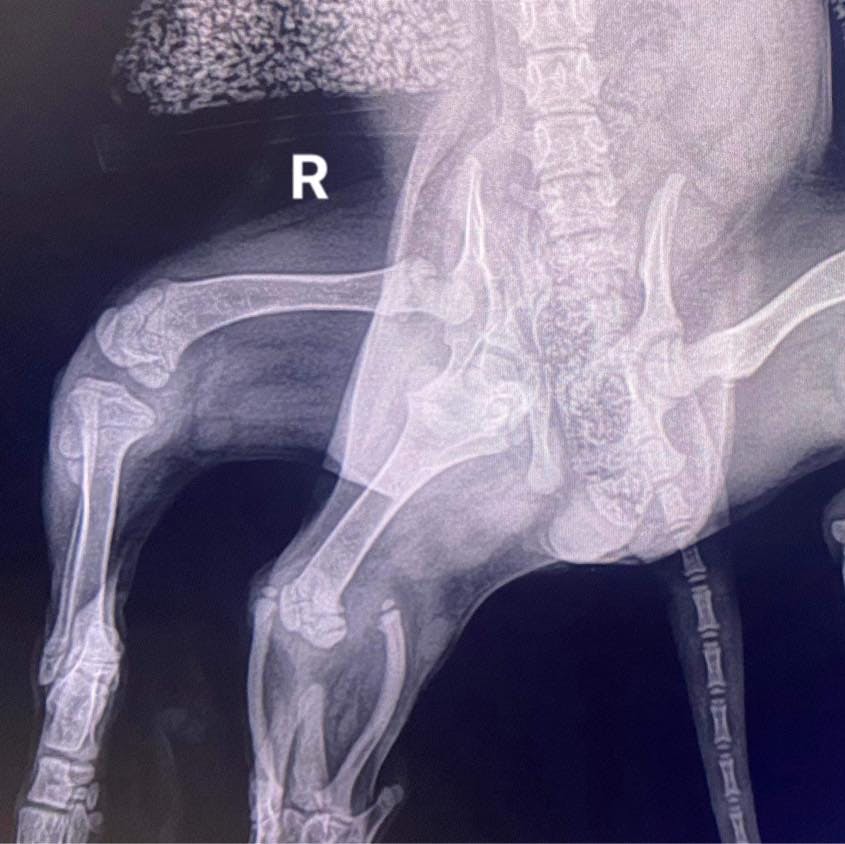

Ariel har nemlig seks ben.

Billeder fra Greenacres Rescue, hvor hunden blev indleveret, viser, at de to ekstra ben sidder fast ved siden af halen.

– Hendes bækken har ikke dannet sig ordentligt på grund af det ekstra hofteled, skriver Greenacre Rescue på Facebook.